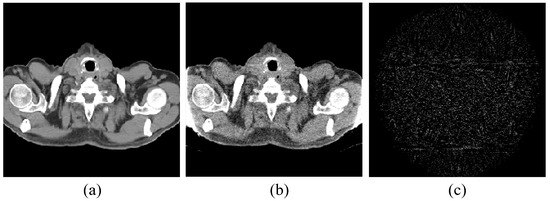

4.1. Image Reconstruction Experiment of Pelvic Image

The first image reconstruction experiment is using a pelvic image to show the feasibility of our algorithm for SVCT reconstruction, as shown in Figure 1. We extracted 80, 64, and 48 views from a full scan and selected parameters empirically. The parameters are set as follows: a = 0.5, γ1 = 0.3, and γ2 = 0.08. Figure 2, Figure 3 and Figure 4 show the ground truth and reconstruction images via FBP, OS-SART, TV, PICCS, TVPI-G, and our method NPICCS. From these figures, it is evident that our algorithm outperforms the other methods in terms of recovering image structures and suppressing noise. Specifically, the FBP and OS-SART results (as shown in Figure 2b,c, Figure 3b,c and Figure 4b,c) contain high levels of noise and artifacts, while TV results (as shown in Figure 2d, Figure 3d and Figure 4d) are characterized by blurring and staircasing effects. The PICCS and TVPI-G methods provide better results than the other approaches because of the introduction of prior information, but image edges are missing as shown in Figure 2e,f, Figure 3e,f and Figure 4e,f. At the same time, it can be seen that our method is able to preserve image edges and suppress noise effectively, as shown in Figure 2g, Figure 3g and Figure 4g.

To compare the recovery of reconstructed image details and edge information, we selected two regions of interest (ROIs) from the 48-view and 64-view reconstructed images and zoomed in to show. The ROIs are labelled with red box as shown in Figure 2a and Figure 3a. The corresponding zoomed-in results are shown in Figure 5. As can be seen from the figure, our algorithm can reconstruct some small image structures shown by the arrows, which are difficult to see by other algorithms. Also, we find that our algorithm performs better in edge retention.

Figure 3. 64 views reconstruction results of pelvic image: (a) ground truth, (b) FBP, (c) OS-SART, (d) TV, (e) PICCS, (f) TVPI-G, and (g) NPICCS. The display window is [−150 250] HU.